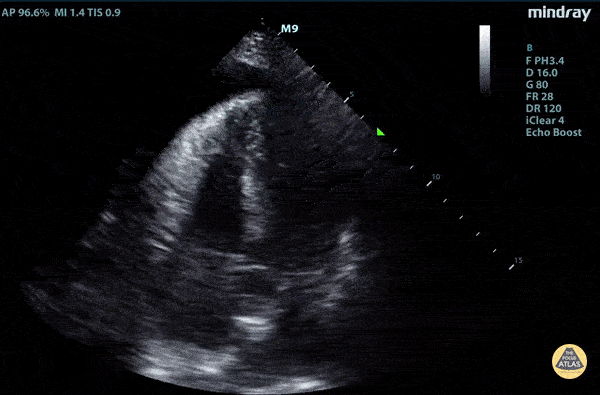

Elderly fellow who had a headache while bike riding, with some leg weakness. No chest or back pain. Stable for hours then came to hospital, suddenly hypotension and drowsy in ER POCUS RUSH Exam performed lead to rapid diagnosis of Aortic Dissection with tamponade. Right ventricular diastolic collapse can be seen. Claire Heslop - Pediatric Emergency Medicine - University of Toronto Hospital for Sick Children